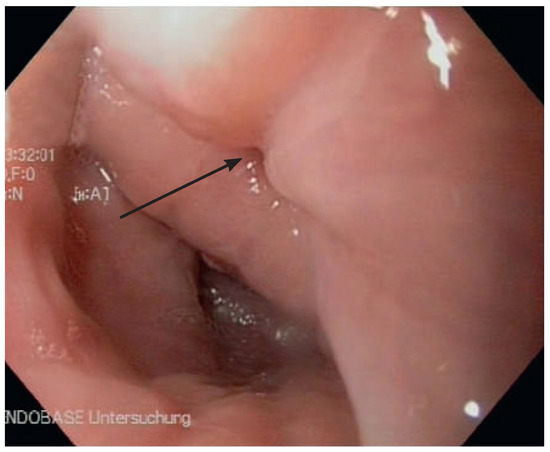

A 41-year-old women with Ebstein’s anomaly required tricuspid valve replacement six years ago. At that time a biological prosthesis was implanted. The tricuspid valve prosthesis became severely stenotic within five years. Instead of re-do surgery, th...